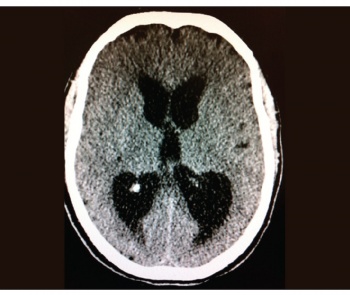

He was mechanically ventilated and remained in the intensive care unit (ICU) for the following 14 days. Investigations showed neutrophil leucocytosis and raised inflammatory markers in his blood. Meningoencephalitis was the working diagnosis from the beginning and he was covered with antimicrobial and antiviral from day one. His CSF analysis showed 35 WBC per/ul (95% lymphocytes), glucose of 3.5mmol (plasma 7.6mmol) and protein of 0.74g/L. Extensive microbiological analysis (including polymerase chain reaction [PCR]) failed to identify any organisms. The repeat CT brain three days later showed areas of low densities at right internal capsule and right temporo-parietal lobe, which are new since the first scan (see Figure 2) and which were suggestive of infarcts, and stroke was a possibility at that stage and was discussed with his family. The course of management, however, remained the same (completed full course of parenteral antibacterial and antiviral) and these areas totally disappeared in the later scans with no adequate explanation to their nature and implication.